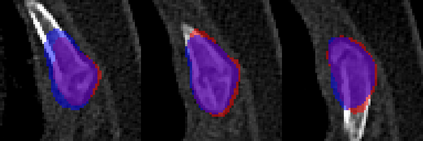

Rib fractures are a common and potentially severe injury that can be challenging and labor-intensive to detect in CT scans. While there have been efforts to address this field, the lack of large-scale annotated datasets and evaluation benchmarks has hindered the development and validation of deep learning algorithms. To address this issue, the RibFrac Challenge was introduced, providing a benchmark dataset of over 5,000 rib fractures from 660 CT scans, with voxel-level instance mask annotations and diagnosis labels for four clinical categories (buckle, nondisplaced, displaced, or segmental). The challenge includes two tracks: a detection (instance segmentation) track evaluated by an FROC-style metric and a classification track evaluated by an F1-style metric. During the MICCAI 2020 challenge period, 243 results were evaluated, and seven teams were invited to participate in the challenge summary. The analysis revealed that several top rib fracture detection solutions achieved performance comparable or even better than human experts. Nevertheless, the current rib fracture classification solutions are hardly clinically applicable, which can be an interesting area in the future. As an active benchmark and research resource, the data and online evaluation of the RibFrac Challenge are available at the challenge website. As an independent contribution, we have also extended our previous internal baseline by incorporating recent advancements in large-scale pretrained networks and point-based rib segmentation techniques. The resulting FracNet+ demonstrates competitive performance in rib fracture detection, which lays a foundation for further research and development in AI-assisted rib fracture detection and diagnosis.